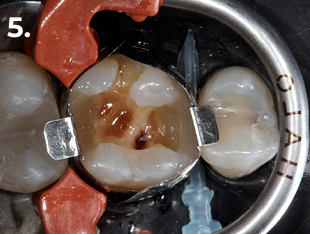

Fig. 5 Conformación de la pared distal para transformar la cavidad en una clase 1

Paciente que acude a consulta refiriendo molestias en la zona del primer cuadrante. La exploración clínica y radiográfica reveló la presencia de una caries profunda distal, estableciéndose el diagnóstico pulpar de pulpitis reversible. Con el objetivo de lograr un adecuado punto de contacto tanto mesial como distal, se procedió a la eliminación completa de la restauración existente. El procedimiento se realizó bajo aislamiento absoluto, utilizando para el encofrado el sistema de matrices seccionales HALO. En la imagen clínica y radiográfica final se observan perfiles de emergencia bien conformados, convexos, así como puntos de contacto adecuados.